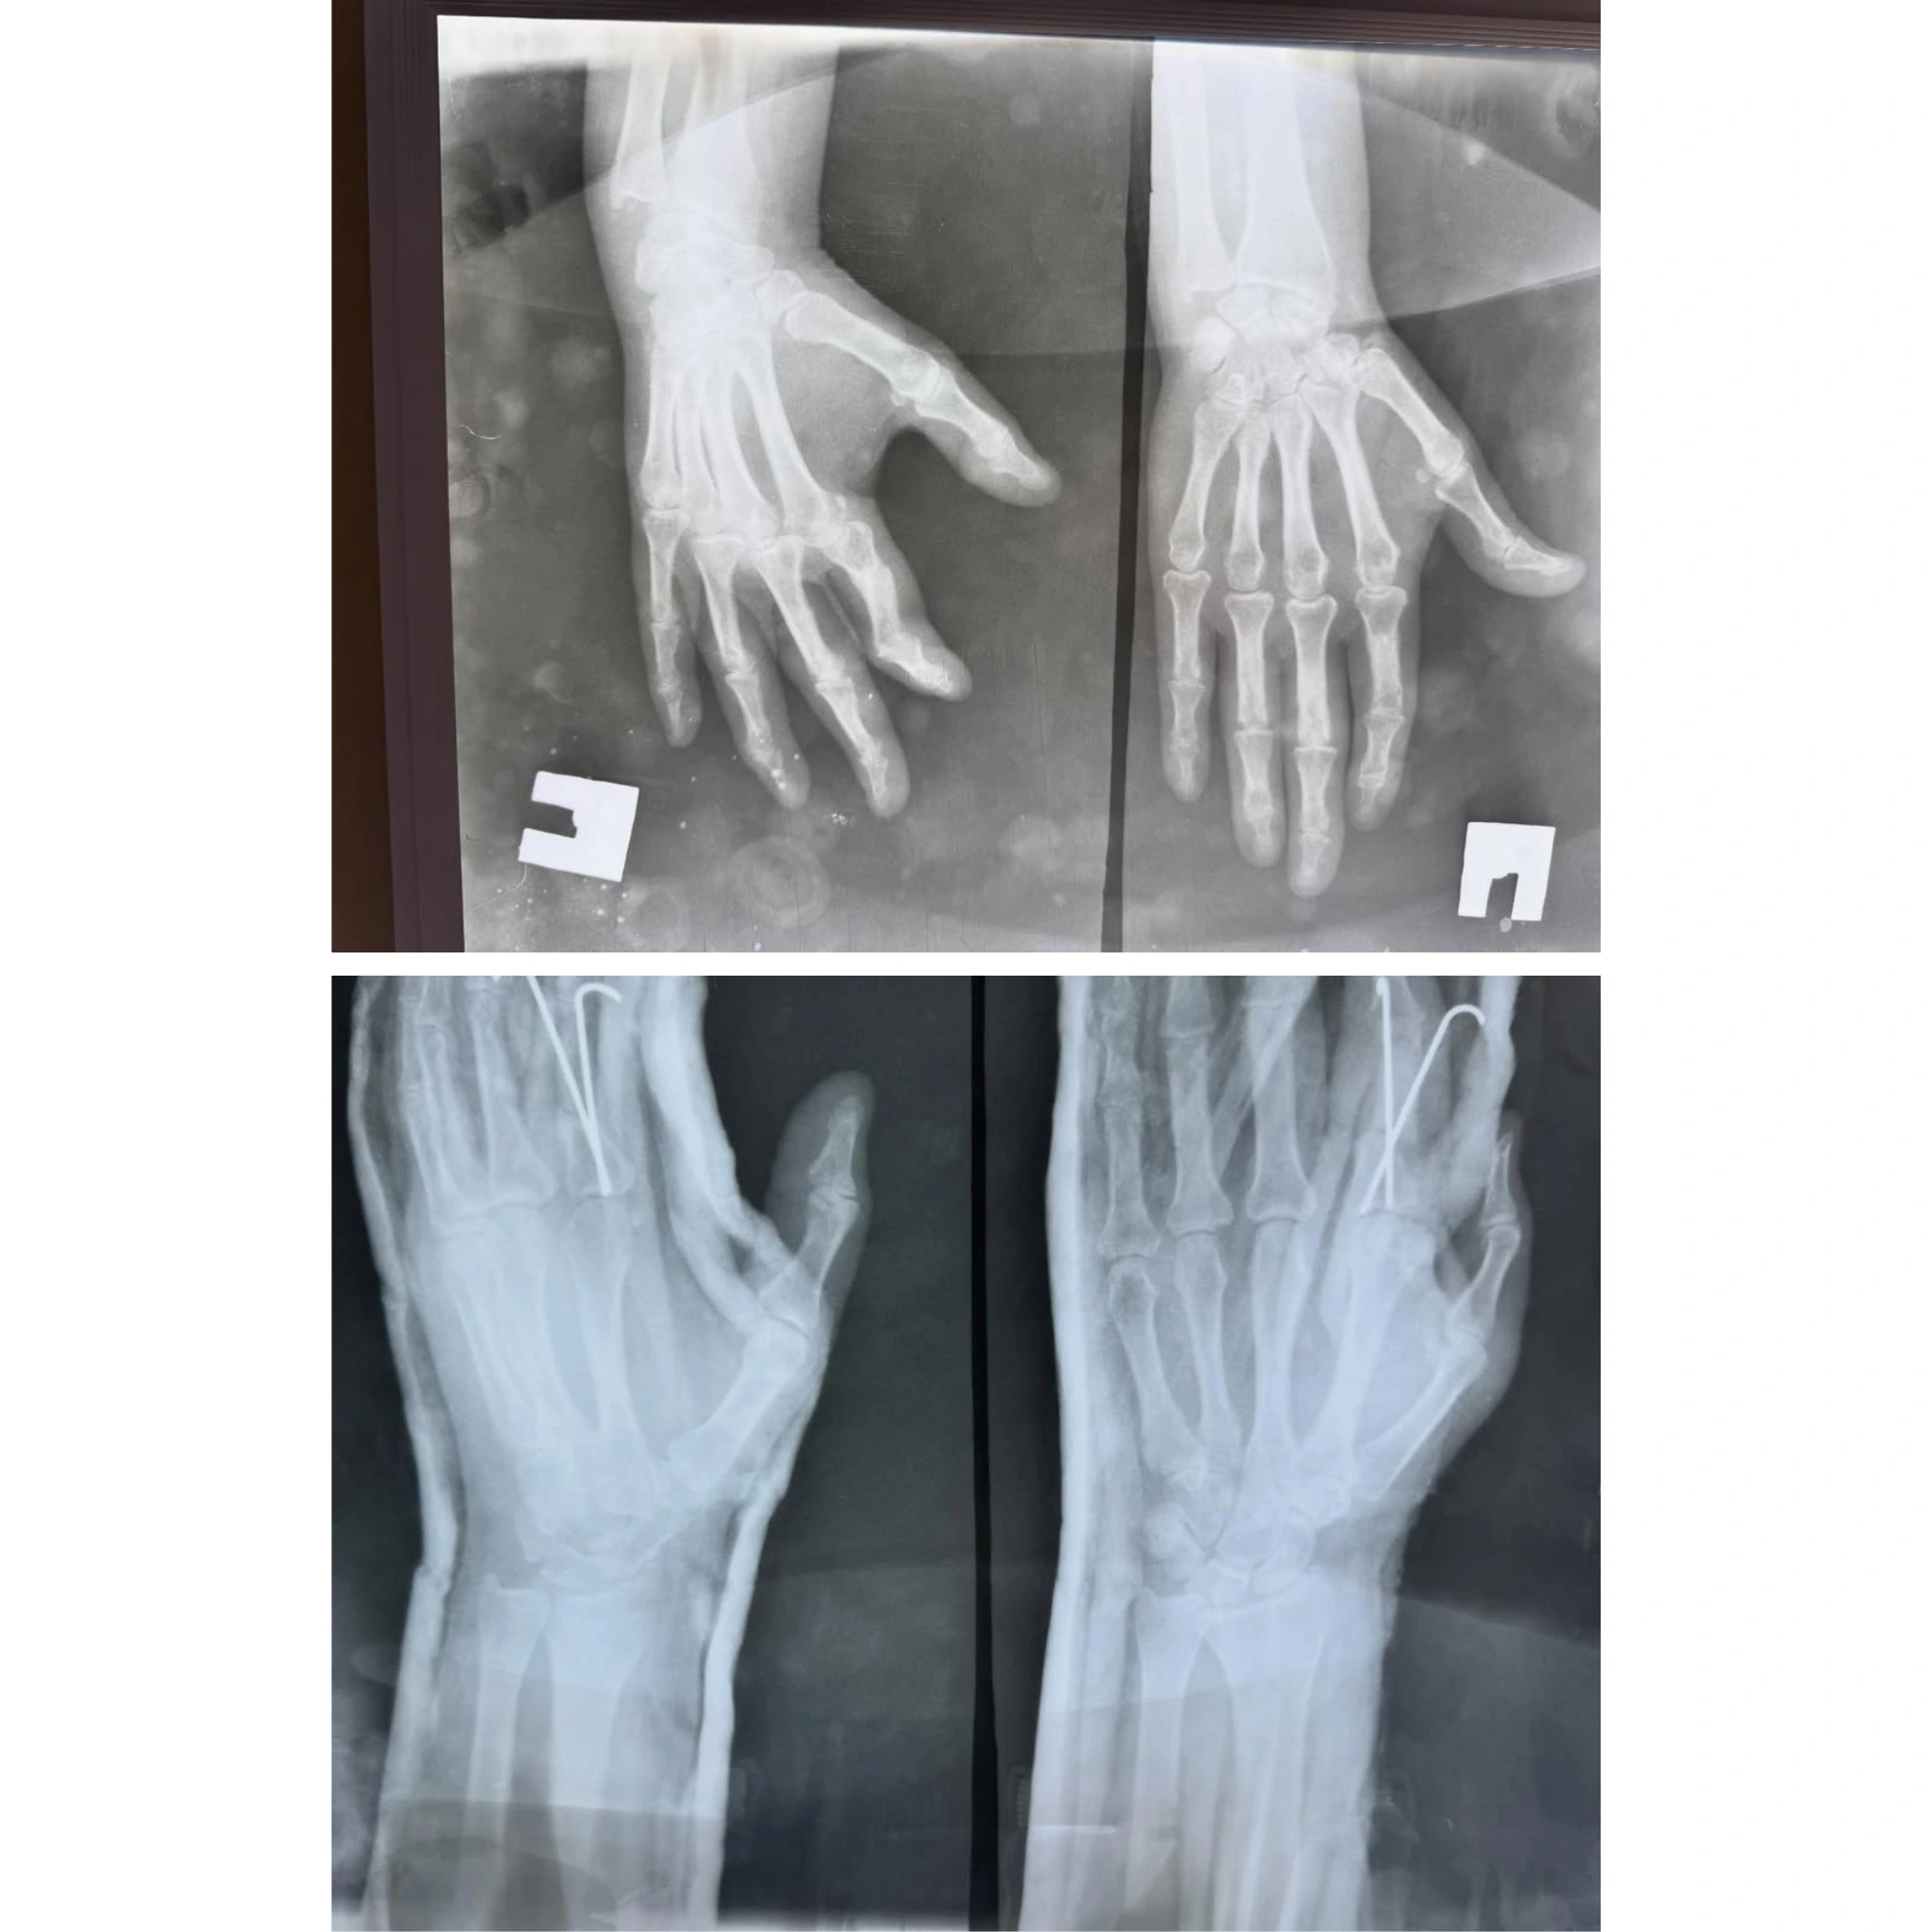

Mürəkkəb sınıqların və oynaq xəstəliklərinin müasir metodlarla bərpasının vizual nəticələri. Pasientlərimizin itirilmiş hərəkət funksiyalarının geri qazanılması bizim ən böyük uğurumuzdur.

Hər bir müalicə prosesi yüksək dəqiqlik və müasir cərrahi standartlara əsaslanır. Bu bölmədə Op. Dr. Aqil Yusubovun əməliyyatxana fəaliyyəti, kliniki iş mühiti və tətbiq etdiyi innovativ metodlarla yaxından tanış ola bilərsiniz.